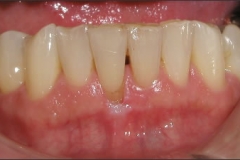

This mouth had recession on just one tooth with very little bone to support the tooth. The area needed support and thickness. The tissue was placed and the area now has thicker tissue to withstand the forces that the patient needs to place on it.

Click on a thumbnail to view the before and after photos.